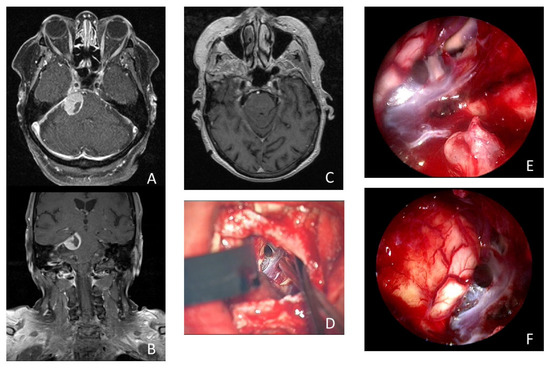

Illustrative case of a 74-year-old woman who presented with 3 months of persistent trigeminal neuralgia, diplopia, and headache. The MRI scan showed a tumorous lesion (15 × 19 × 16 mm) in the cerebellopontine angle with contact with the tentorium and Meckel’s cave in axial (A) and coronal (B) imaging. Postoperative MRI showed no remnant tumor tissue (C). (D) Microscopic view of the surgical field after resection of the meningioma. Intraoperative inspection with 30° endoscope revealed remnant tumor tissue (*) in the internal acoustic meatus (E). Intraoperative inspection with 30° endoscope into the prepontine space without remnant tumor tissue (F).

A 74-year-old woman presented with 3 months of persistent trigeminal neuralgia, diplopia, and headache. The MRI scan showed a tumorous lesion (15 × 19 × 16 mm) in the cerebellopontine angle with contact with the tentorium and Meckel’s cave. Gross total resection of the tumor was achieved using an endoscopic-assisted microsurgical retrosigmoidal approach in a semi-sitting positioning. Upon histopathologic examination, a meningotheliomatous meningioma WHO I was found. The patient’s complaints disappeared directly after surgery. She received MR imaging during follow up at 6, 12, and 24 months after surgery, showing no recurrence and no remnant tumor tissue (see Figure 3 and Supplementary Video S2).